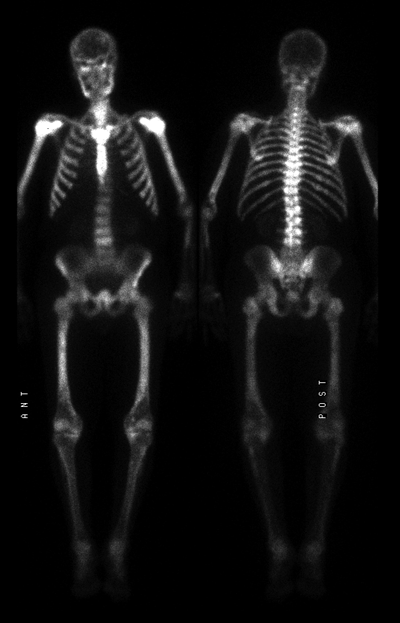

Prostate Cancer Diagnostic Workup / MIR Teaching file case bs119 / One in seven men in the united states will receive a prostate cancer diagnosis during his lifetime.. Here are 10 more facts about prostate cancer. I may get the prostate cancer, which diagnostic test is the most common one, i mean, the classic one? Advertisement from conditions to treatments to surgical devices and more, we've put everything you need to know about u. A description of genomic diagnostic testing for prostate cancer to help patients make informed choices about treatments. One in seven men in the united states will receive a prostate cancer diagnosis during his lifetime.